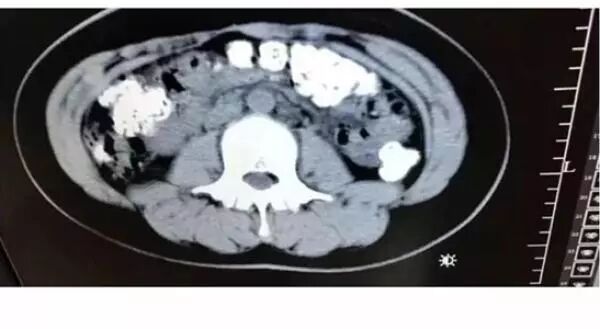

14岁女孩喝了珍珠奶茶后,五天没有排便,还肚子疼,CT检查发现胃肠道布满一颗颗圆圆的高密度阴影——没有消化的“珍珠”。

5月28日晚,女孩小沈(化名)在父母陪同下到浙江诸暨市人民医院急诊,说肚子疼,几天无法排便,也吃不下东西。接诊医生张楼炜见她肚子鼓鼓的,便安排了腹部CT,检查结果让他一惊:患者胃部、横结肠、升结肠、降结肠、乙状结肠,一直到肛门,全是颗粒状阴影,足有百余颗